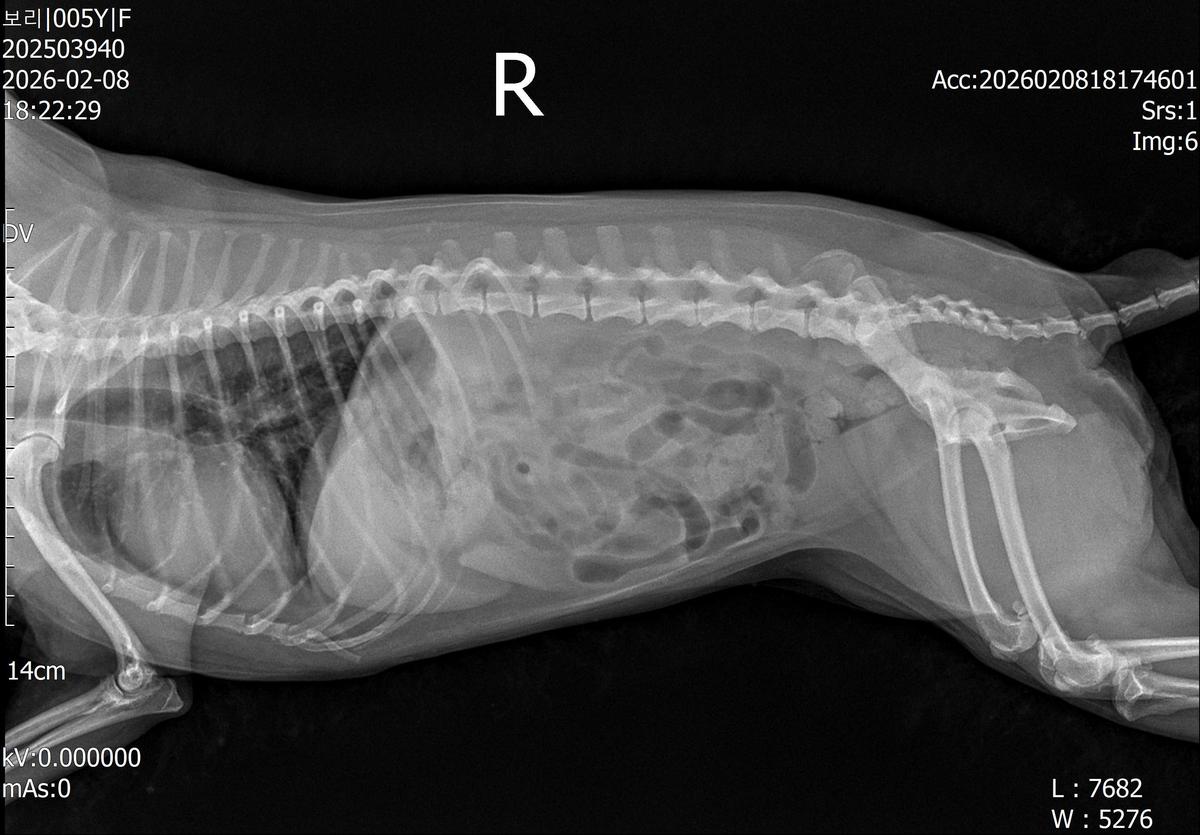

강아지 슬개골탈구 진단 받았습니다 몇군데 병원을 다녀봤는데 진단이 달라 궁금해서 질문 해봅니다 일단 저희 강아지는 오른쪽 다리를 갑자기 들고 다니고 절어 병원을 방문하게 되었고요 왼쪽은 증상이 없지만 오른쪽만 있는 상태였습니다 첫번째랑 두번째 병원에서는 슬개골 탈구 진행중이고 왼쪽이 3기 오른쪽이 2기 정도라고 했습니다 하지만 왼쪽은 아예 빠져있어 증상도 없고 아파하지도 않는다고 했고 오른쪽은 빠졌다 안빠졌다 해서 증상이 있다고 했고 십자인대가 파열된 걸론 보이지 않는다고 했습니다 그래서 양쪽 슬개골탈구 수술만 진행하면 된다고 했고요 근데 세번째 병원에서는 둘다 왼쪽이 좀 더 심한 슬개골 탈구 3기 정도라고 했고 오른쪽만 십자인대 부분파열이 보인다고 했습니다 그래서 십자인대 파열이 아닌 왼쪽은 굳이 수술할 필요가 없고 나중에 십자인대 파열이 오거나 증상이 나타나면 그때 수술하면 된다고 했습니다 그래서 오른쪽 슬개골탈구 수술과 tplo를 하는 방식으로 수술을 한다고 했습니다 여기서 궁금한점은 1. 십자인대 파열이 사진상으론 보이지 않는다고 하는데 사진상으로 알 수 있는 건가요? 2. 십자인대 파열이 아니면 슬개골탈구 수술을 굳이 할 필요 없다고 하셨는데 맞는 건가요? 3. 꼭 슬개골탈구와 십자인대 수술을 같이 해야 결과과 더 좋아지나요? 4. 사진상으로 십자인대와 슬개골 수술을 같이 해야할까요? 5. tplo 수술방법이 가장 안전하고 좋은 수술방법인가요? 6. 슬개골탈구로 인해 십자인대가 끊어지는건 아니라고 들었는데 맞나요? 슬개골 탈구 수술로 십자인대를 예방할 수 있나요?